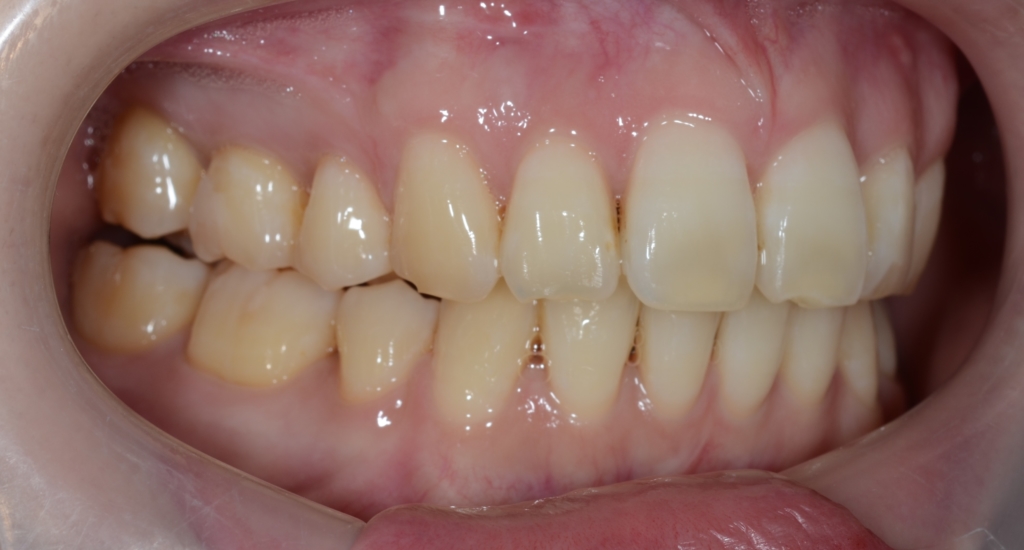

【診断】

#1.上顎前突

#2.顎と歯の大きさの不調和による叢生

#3.ガミースマイル

と診断しました。

*歯並びの写真で見ると「出っ歯」であるとは分かり難いですが、頭部全体のレントゲン写真を見ると、出っ歯であることがハッキリと分かります。

【治療方針】

1.上下左右の奥歯を抜歯をしてスペースを作り、前歯の乱れをきれいにする

2.アンカースクリューを用いて、上顎前歯を圧下させてガミースマイルの改善を図る

3.並行して、下の前歯を最大限に後方へ移動

4.その後、上の前歯を残る隙間分最大限に引っ込める

5.必要ならアンカースクリューを追加して上の歯列をより後方へ引っ込める

という治療計画にて、矯正を進めることにしました。